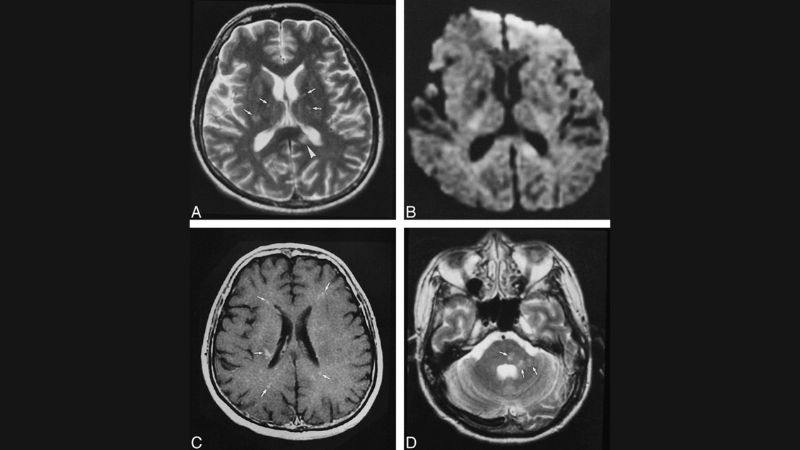

Image description of Nipah Virus Encephalitis

Nipah Virus Encephalitis is a rare but deadly viral infection transmitted from bats or animals to humans. It primarily affects the brain, causing severe neurological and respiratory symptoms. Awareness and prevention are crucial to controlling outbreaks.